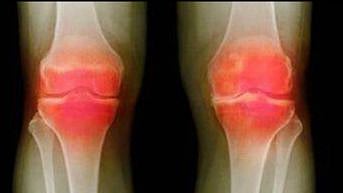

गाउट होण्याचे मुख्य कारण म्हणजे यूरिक ऍसिडचे प्रमाण वाढणे. कारण वाढलेले युरिक अॅसिड क्रिस्टल्स तयार होऊन सांध्यांमध्ये जमा होऊ लागतात. त्यामुळे सांधे जाम होतात आणि सूज येऊन वेदना वाढू लागतात.

अलीकडील संशोधनानुसार, यूरिक ऍसिडचे हे क्रिस्टल्स हृदय आणि मेंदूला होणार रक्तपुरवठा रोखतात. ज्यामुळे हृदयविकाराचा झटका आणि पक्षाघात देखील होऊ शकतो.

युरिक ऍसिड वाढल्यामुळे त्याचे रुपांतर क्रिस्टल्समध्ये होते. सांंध्यांमध्ये क्रिस्टल्स जमा होतात. सांधे कडक होऊ लागतात.

संधिवात लक्षणे काय आहेत ?

सांधेदुखी-क्लॅम्प, गुडघ्यांमध्ये सूज येणे, मोडलेली हाडे, त्वचा लाल होणे.